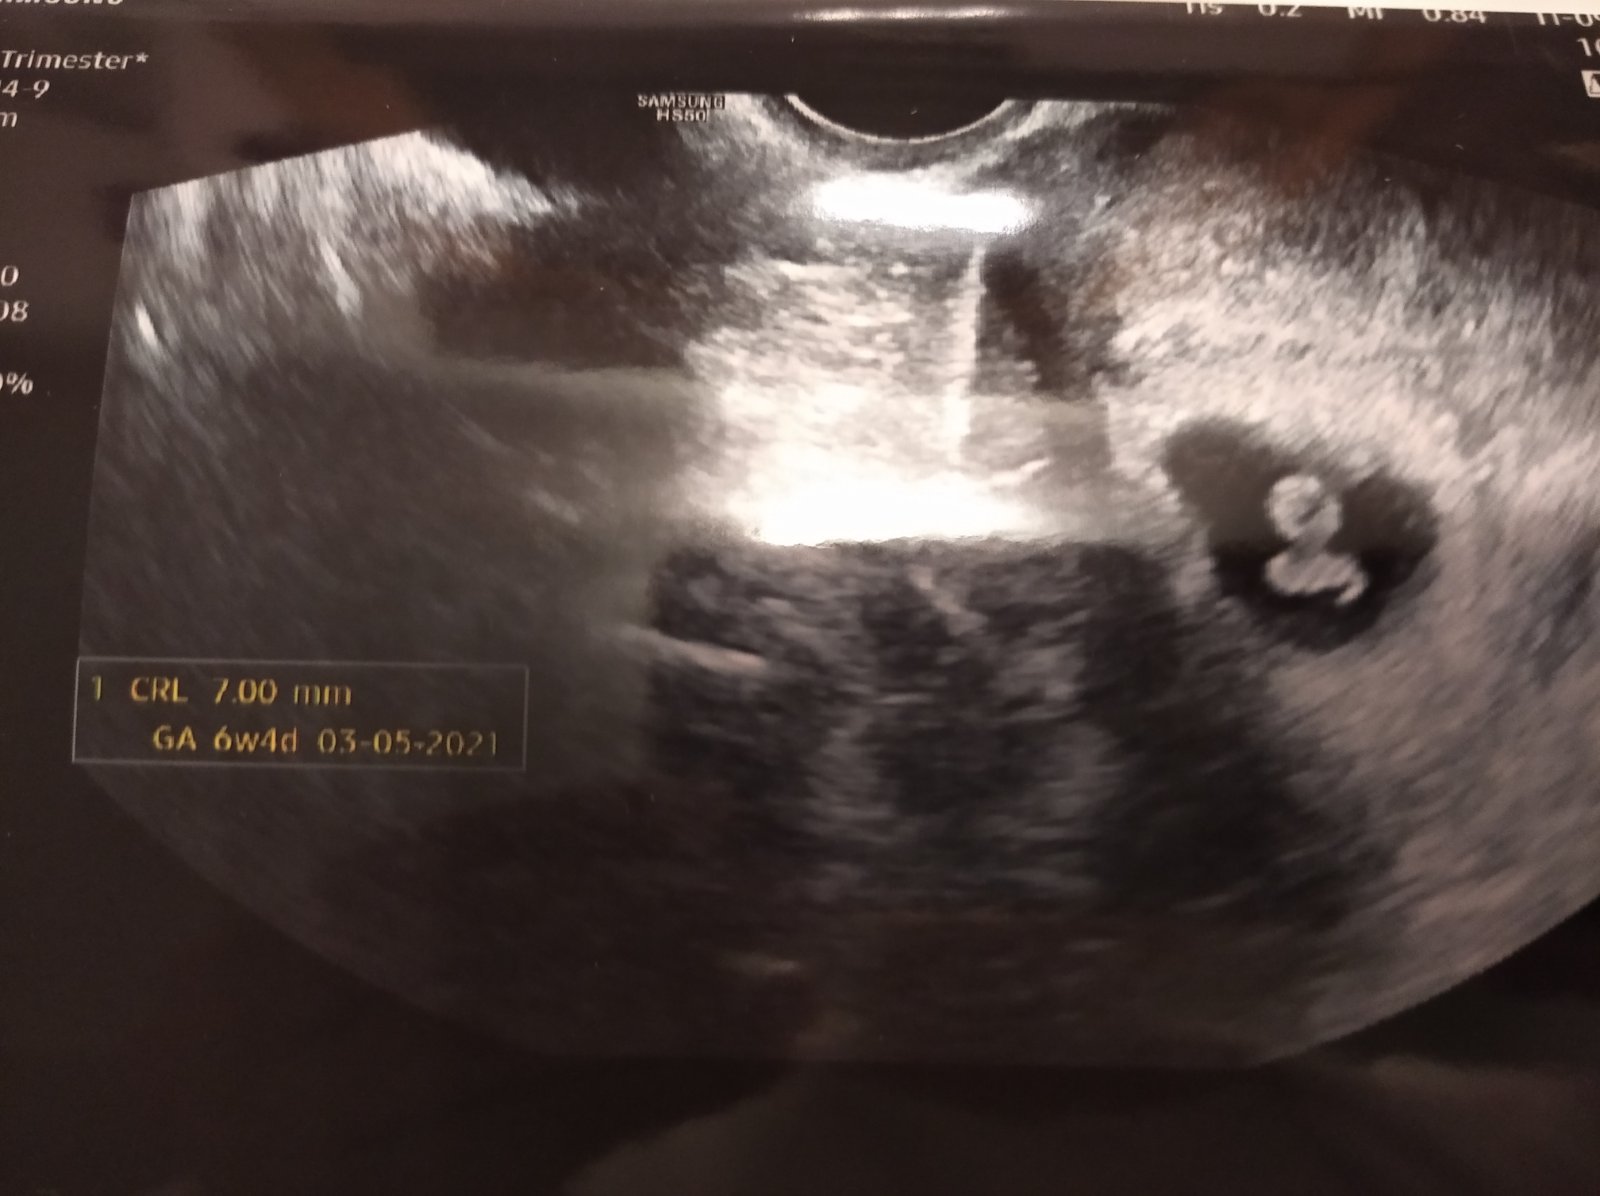

Já byla v pátek 6+4 a už i srdíčko.

Fotku nemám, prý nic nejde vidět 🤦‍♀️ ale já si drze aspoň z dálky vyfotila kartu 😁

Jinak odpovídá o 5 dní méně, takže termín zatím 3.5. ale vše vypadá v pořádku a kontrola za měsíc v poradně a už screening 😊